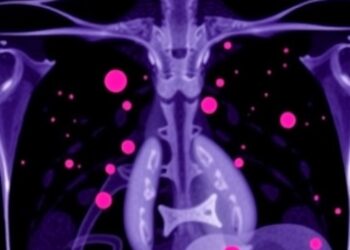

SPARK Trial: New Treatment for Triple-Negative Breast Cancer

In a groundbreaking advance that could shift the paradigm of triple-negative breast cancer therapy, researchers have unveiled promising results from ...